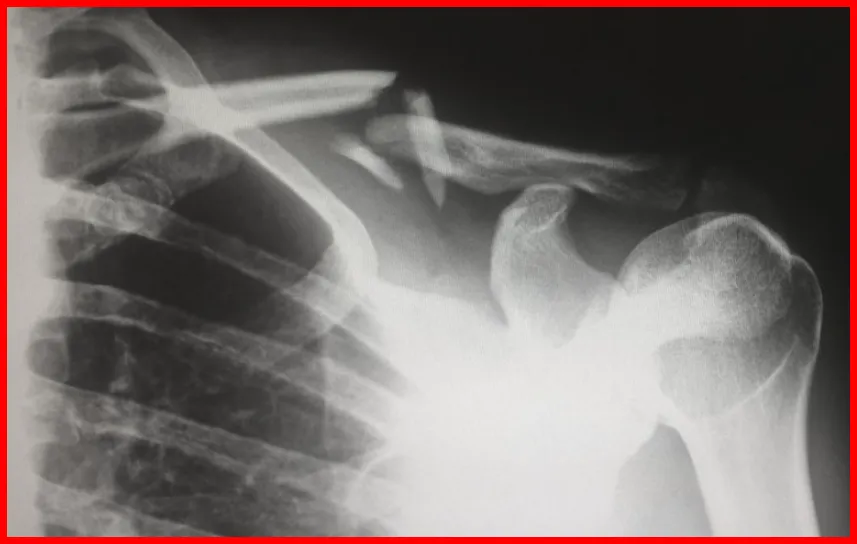

대표적인 급여 항목 예시

- 엑스레이 검사